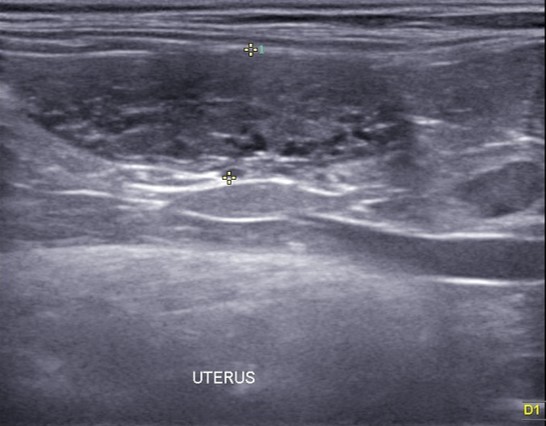

이어 진행된 초음파 검사에서는 자궁축농증으로 인해 내막이 두꺼워지고 크기가 커지는 염증성 변화가 진행되고 있었습니다.

✔US 양 자궁내막증식, 자궁각내삼출물에 의한 심한 확장소견